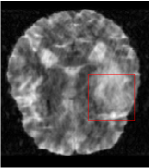

Qualitative comparison between conventional and Meta-learning methods are shown in Figure 1 and 3, which display the reconstructed MR images of the same slice for T1 and T2 respectively, we label the zoomed-in details of HGG in the red boxes. We observe the evidence that conventional learning is more blurry and lost sharp edges, especially in lower CS ratios. From the point-wise error map, we find meta-learning has the ability to reduce noises especially in some detailed and complicated regions comparing to conventional learning.

In this section, we test the generalizability of the proposed model that tests on unseen tasks. We fix the well-trained task-invariant parameter and only train for sampling ratios 15%, 25% and 35% with radio masks and sampling ratios 10%, 20%, 30% and 40% with Cartesian masks. In this experiment, we only used 100 training data for each CS ratio and apply a total of 50 epochs. The averaged evaluation values and standard deviations are listed in Table 5.4 and 5.4 for reconstructed T1 and T2 brain images respectively that proceed with radio masks, and Table 5.4 shows the qualitative performance for reconstructed T2 brain image that applied random Cartesian sampling masks. In T1 image reconstruction results, meta-learning improved 1.6921 dB in PSNR for 15% CS ratio, 1.6608 dB for 25% CS ratio, and 0.5764 dB for 35% comparing to the conventional method, which in the tendency that the level of reconstruction quality for lower CS ratios improved more than higher CS ratios. A similar trend happens in T2 reconstruction results with different sampling masks. The qualitative comparisons are illustrated in Figure 2, 4 and 5 for T1 and T2 images tested in skewed CS ratios in radio masks, and T2 images tested in Cartesian masks with regular CS ratios respectively. In the experiments that conducted with radio masks, meta-learning is superior to conventional learning especially at CS ratio 15%, one can observe that the detailed region in red boxes keeps edges and is more close to the true image, while conventional method reconstructions are hazier and lost details in some complicated tissue. The point-wise error map also indicates that Meta-learning has the ability to suppress noises.

Training with Cartesian masks is more difficult than radio masks, especially for conventional learning where the network is not very deep since the network only applied three convolutions each with four kernels. Table 5.4 indicates that the average performance of meta-learning improved about 1.87 dB comparing to conventional methods with T2 brain images. These results further demonstrate that meta-learning has the benefit of parameter efficiency, the performance is much better than conventional learning even if we apply a shallow network with small size of training data.